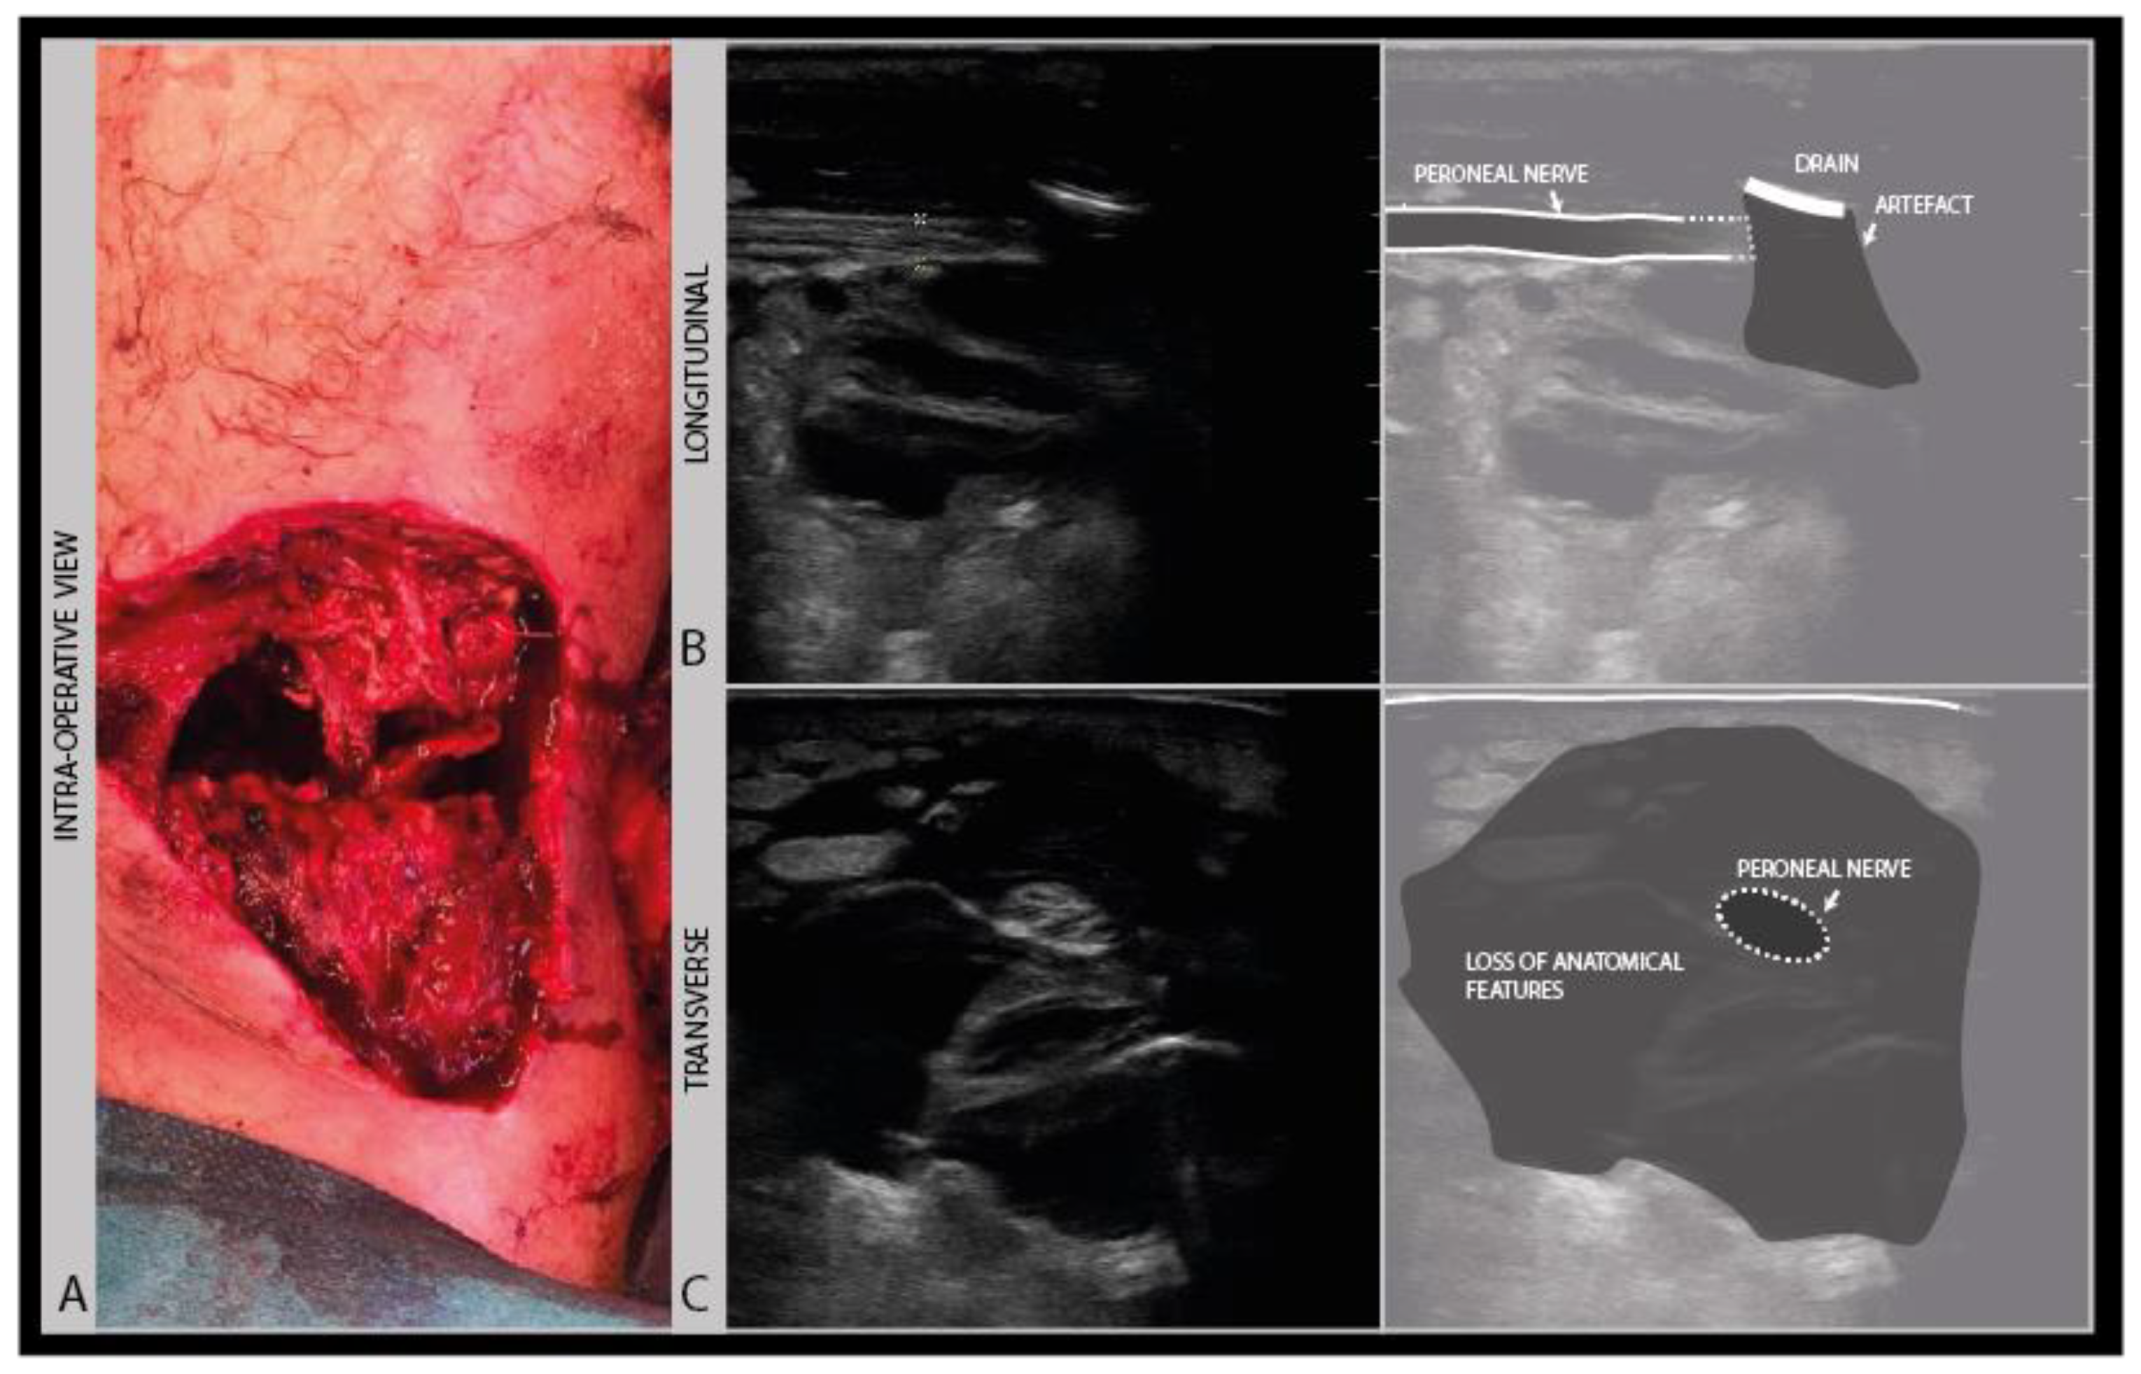

As a standard in neurological nerve ultrasound, transverse imaging is performed for the anatomical identification of the nerve of interest, and to assess its size and architecture for abnormalities. The international agreement is that the nerve size is best measured as a cross-sectional area (CSA) of the nerve traced within the hyperechoic outer epineurial rim [17]. Tracing within the epineurium is the best way to standardize the measurements across patients and over time, as the outer parts of the epineurium blend into surrounding epimysium and fascial structures, which hampers the accurate delineation of the nerve. CSA reference values are available for many nerves [18]. Nerve size increases during growth, so for schoolchildren it is advisable to adhere to a reference that is 50–75% of the adult size depending on age [19].

To assess the nerves for abnormality, it is strongly advised to scan the nerve all the way along its accessible length, looking for sudden changes in size or appearance. When an abnormality is found, it is advisable to also twist the probe 90° around and make a longitudinal image of the lesion site. When measuring neuroma sizes, placing several diameter markers proximal, at and caudal to the lesion site may be helpful (Figure 3).

Figure 3.

Image examples of transverse cross-sectional area (CSA) (A) versus longitudinal diameter measurement (B). A: distal ulnar neuroma; B: distal median nerve neuroma (adult male with a crush injury of the distal forearm). ULN = ulnar nerve.